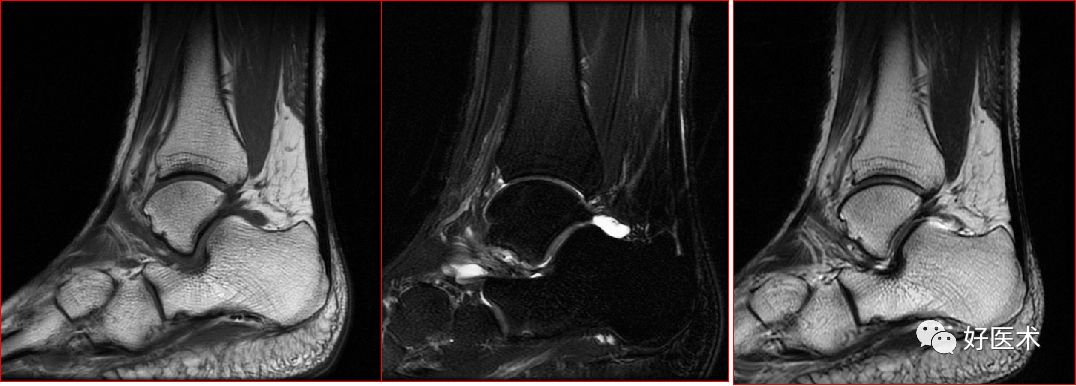

跟腱损伤

跟腱正常表现

跟腱运动损伤

跟腱附着处炎症

跟腱部分(完全)撕裂:跟腱最厚处前后径一般小于6mm,在踝关节上方2 – 6cm处跟腱纤维交叉走行,血液供应减少,易撕裂

慢性跟腱炎

跟腱炎症

慢性跟腱炎并跟腱部分撕裂

跟腱撕裂